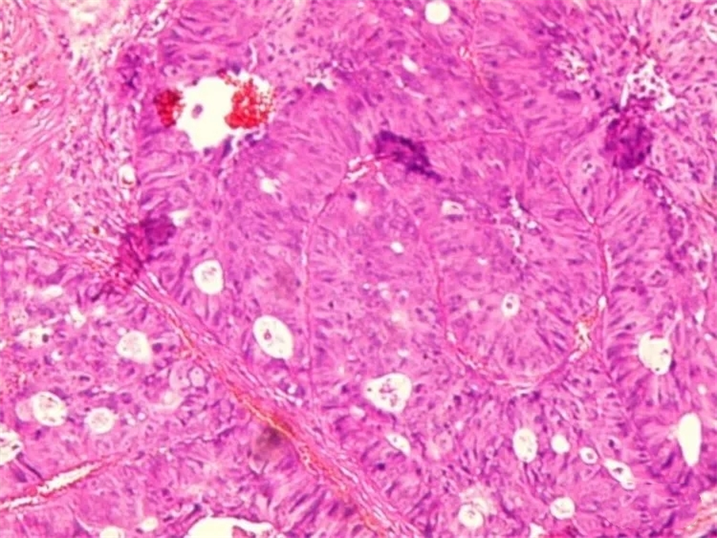

病理结果绒毛管状腺瘤,局灶癌变。

这个病例显示,若患者及时就诊,医生第一时间发现并切除息肉,同时,患者定期复查,即可避免息肉恶变,未来形成结直肠癌。与此同时,40岁以上人群还应每年做一次大便潜血检查,凡有便血或大便习惯改变,直肠指检无异常发现者,结肠癌的检查应常规配合进行纤维结肠镜检查。不但能够发现结肠各种类型的病变,而且可以采取组织活检,明确诊断,以免漏诊或误诊。